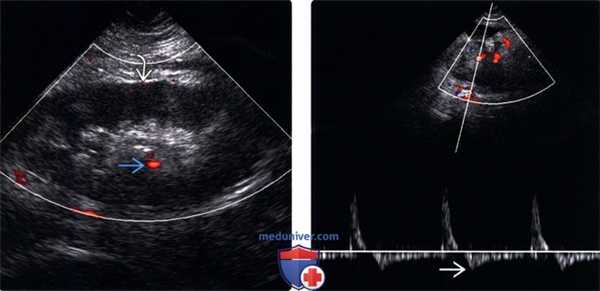

(Левый) Продольный УЗ срез с энергетической допплерографией трансплантата почки у пациента с жалобами на боль и анурию. Визуализируется минимальный цветовой поток в отечном трансплантате.

(Правый) На продольном УЗ срезе с допплерографией у того же пациента визуализируется измененная спектрограмма сегментарной артерии с узкими систолическими пиками и реверсией кровотока в диастолу. Почечная вена тромбирована.